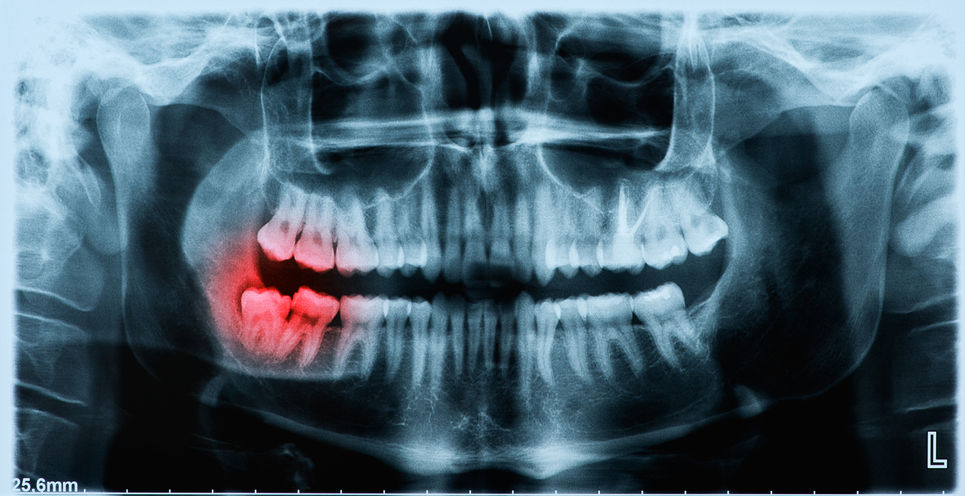

Details